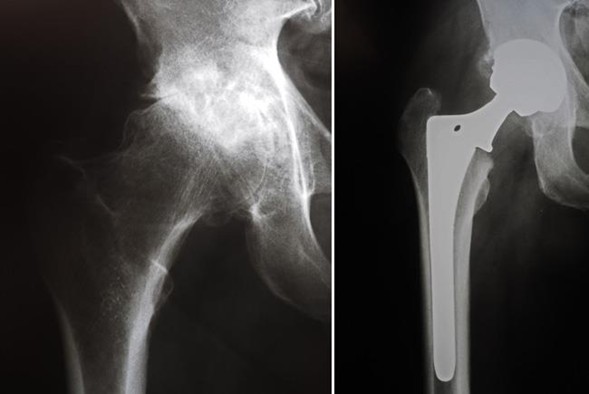

Radiografía antes y después del reemplazo total de cadera. En este caso, se usaron componentes no cementados.